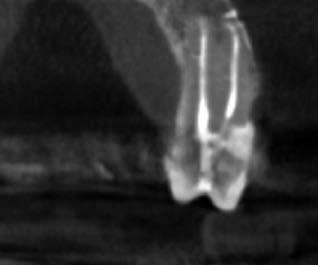

4. a ábra: A CBCT felvétel igazolja, hogy a jobb felső nagymetszőfog megfelelő pozícióba került. Az ínyszél lefutása kedvező, a fog gyökere körül elfogadható mennyiségű csontállomány ábrázolódik, valamint a gyökérfelszívódás mértéke sem túl kifejezett.

4. b ábra: A panoráma röntgenfelvétel is alátámasztja a CBCT felvételen látottakat.

4. c ábra: Az intraorális felvételen megfelelő fogpozíciók és kedvező ínyszéli lefutás ábrázolódik.

6 hónapon keresztül tartott. Ennek megfelelően a fog körül található szövetek a felszabadítás, valamint a havi kontrollok során 975 nm-es (több mint 25 J/cm2 energiasűrűség) és 660 nm-es hullámhosszúságú (12–18 J/cm2 energiasűrűség) lézersugarakkal is megvilágításra kerültek. Az impaktálódott fogat megközelítőleg 7 hónap alatt tudtuk megfelelő pozícióba mozgatni (3. ábra). Az orthodoncia kezelés aktív szakasza 18 hónapon keresztül tartott. A fogívek végső nivellálását és a fogak végleges pozícióba rendezését 0.018 × 0.025-ös acélívekkel végeztük.

A kezelés befejezésekor a páciens mosolya drámai mértékben javult, továbbá a frontfogak elhelyezkedése és az ínyszél lefutása is szemmel látható módon kedvezőbbé vált (4. ábra). A kezelés végén készült CBCT felvétel nem mutatta

csontfelszívódás jelenlétét, és csupán minimális mértékű gyökérfelszívódás bekövetkezését igazolta.